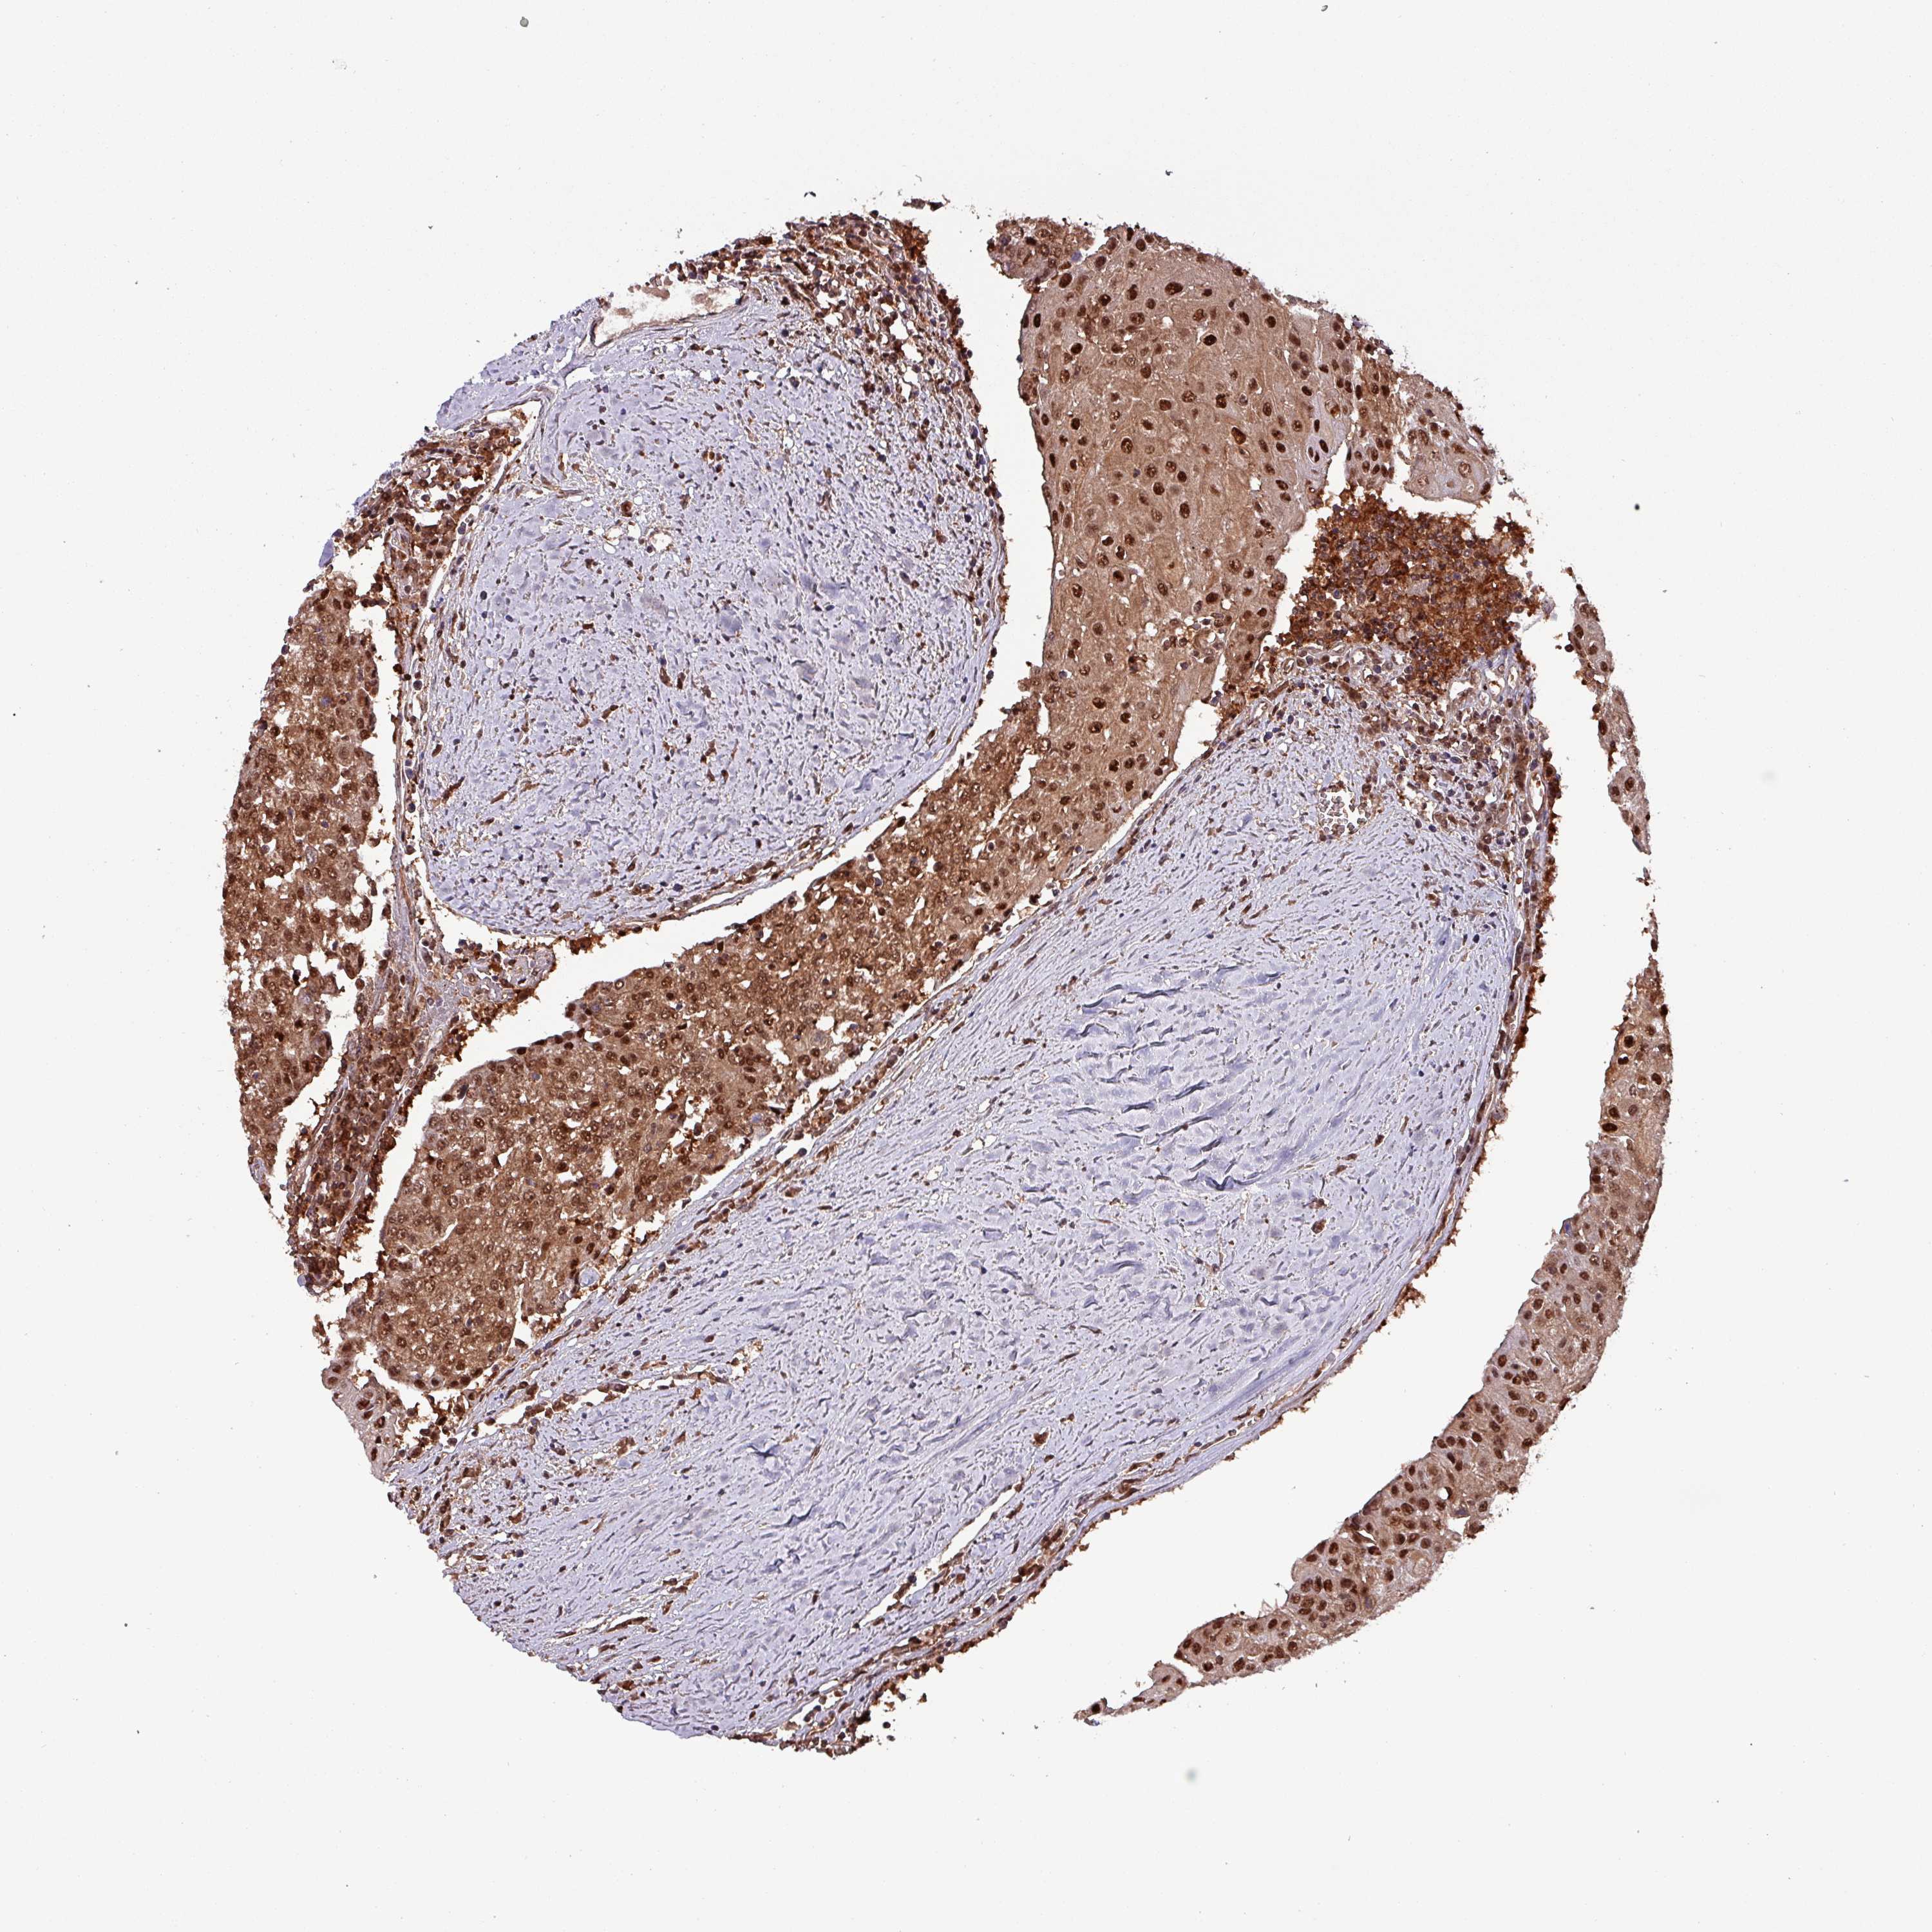

UROTHELIAL CANCER - Protein expressioni

A mouse-over function shows sample information and annotation data. Click on an image to view it in a full screen mode. Samples can be filtered based on level of antibody staining by selecting one or several of the following categories: high, medium, low and not detected. The assay and annotation is described here.

Note that samples used for immunohistochemistry by the Human Protein Atlas do not correspond to samples in the TCGA dataset.

Antibody stainingi

Antibody staining in the annotated cell types in the current human tissue is reported as not detected, low, medium, or high, based on conventional immunohistochemistry profiling in selected tissues. This score is based on the combination of the staining intensity and fraction of stained cells.

Each image is clickable and will lead to virtual microscopy that enables deeper exploration of all samples and also displays staining intensity scores, fraction scores and subcellular localization as well as patient and tissue information for each sample.

Antibody HPA046995

Antibody HPA050327

Staining

High

Medium

Low

Not detected

Intensity

Strong

Moderate

Weak

Negative

Quantity

>75%

75%-25%

<25%

None

Location

Nuclear

Cytoplasmic/membranous

Cytoplasmic/membranous,nuclear

Urothelial carcinoma, High grade

Urothelial carcinoma, Low grade

Urothelial carcinoma, NOS